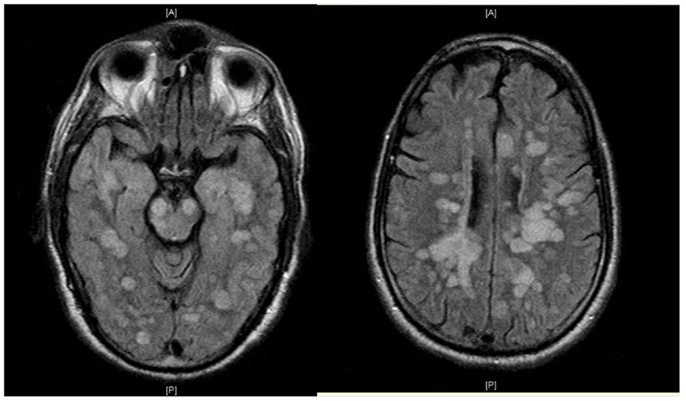

Фотографии объектов и элементов, связанных с цифрой 3

Раздел: Картинки на заметку